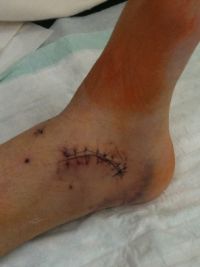

Der Gips wird erneuert und das ganze Ausmaß

der Verletzung wird sichtbar …

Der Patient prüft zum ersten Mal die Wunde und begutachtet die Spuren der OP: Lange Narben „zieren“ ab sofort den Fuß. Auch eine Kinderunfallversicherung kann einen Unfall nicht verhindern und schon gar nicht rückgängig machen. Aber es ist gut zu wissen, dass für den Fall der Fälle ausreichende Vorsorge getroffen wurde.